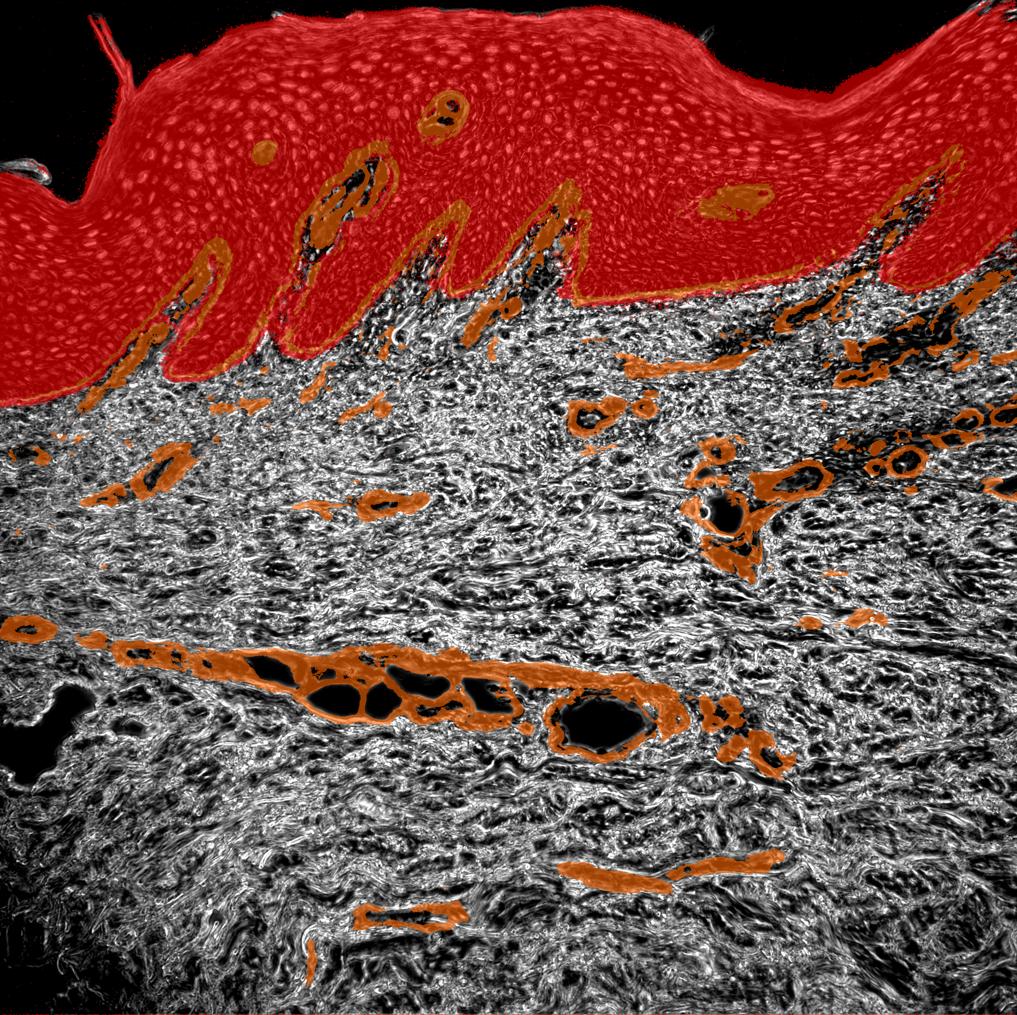

Phase contrast image

Keratinocytes

Collagen

Vessels

Psoriatic Skin

Human tissue section

Autoimmune loop